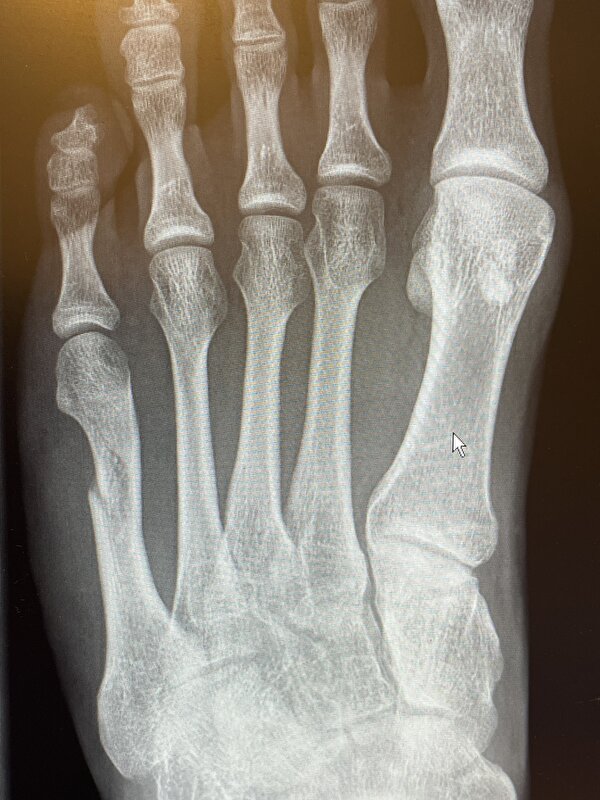

Jet schreef:Nobel, hoort daar ook nog een tussenwervelschijf te zitten die er nu niet of nauwelijks meer is? En zie ik scoliose?

En die van die voet: hoort die grote teen zo te staan?

Bij de voet foto is er niks met de grote teen aan de hand. Bij de kleine teen het middenvoetsbeentje gebroken.

En beter dat de grote teen zo hoort!